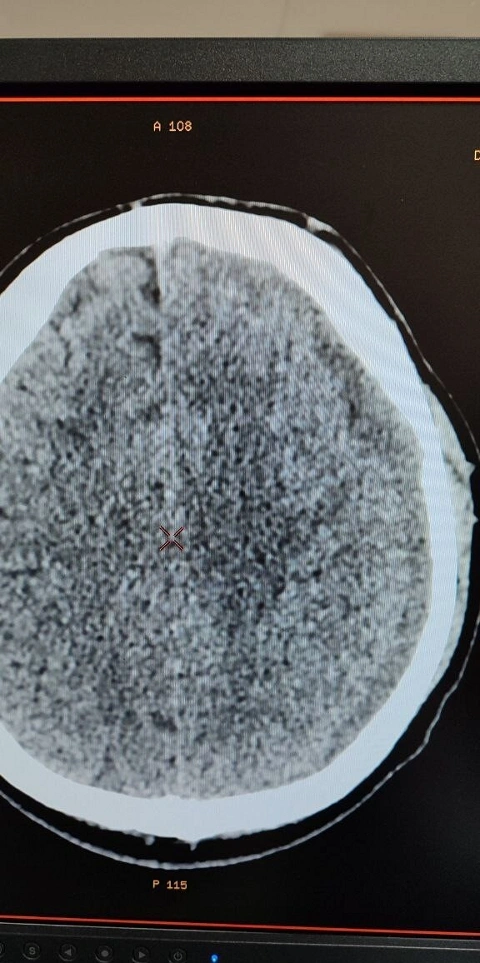

Как сообщает Балаковская городская клиническая больница (БГКБ), в приемный покой в Балаково 18 декабря поступил 39-летний мужчина, у которого диагностировали очаги контузии обоих полушарий головного мозга и небольшого объема субдуральная гематома слева, вызвавшая значительное смещение структур головного мозга.

По информации БГКБ, операция была проведена 25 декабря, и уже через 4 суток контрольная СКТ показала значительный регресс гематомы (не менее 20%) и уменьшение смещения мозга с 4 мм до 2 мм. Пациент постепенно идет на поправку, и за этим процессом внимательно следят врачи. И балаковские медики, в очередной раз доказали, что они могут творить настоящие чудеса.